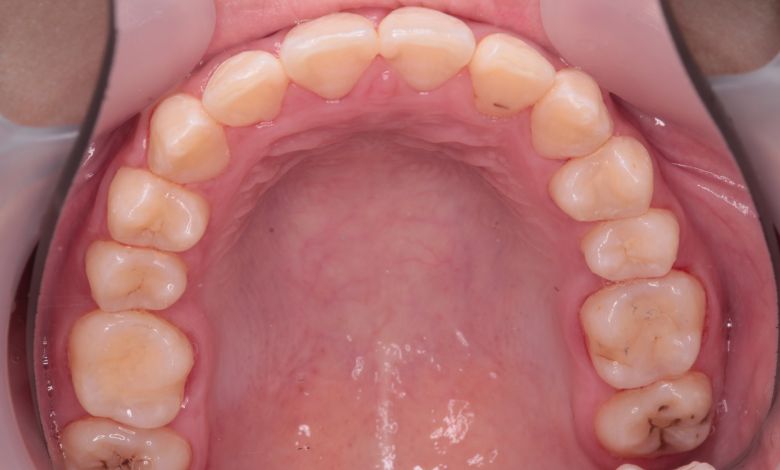

正常な咬合関係が確立され、前歯の自然なアーチと歯軸も整い、歯列全体が滑らかなカーブを描く美しい歯並びに

精密検査の結果、当院では抜歯を行わず、歯列弓の拡大によってスペースを確保し、非抜歯での矯正治療を選択しました。歯列の叢生(ガタガタ)は解消され、機能的かつ審美的に優れた咬合が得られました。

叢生が解消され、歯列全体にわたり滑らかで調和のとれた配列が得られています

歯列弓はV字型から自然でゆったりとしたU字型へと広がり、唇側に転位していた犬歯も正しい歯列内に整列されています。